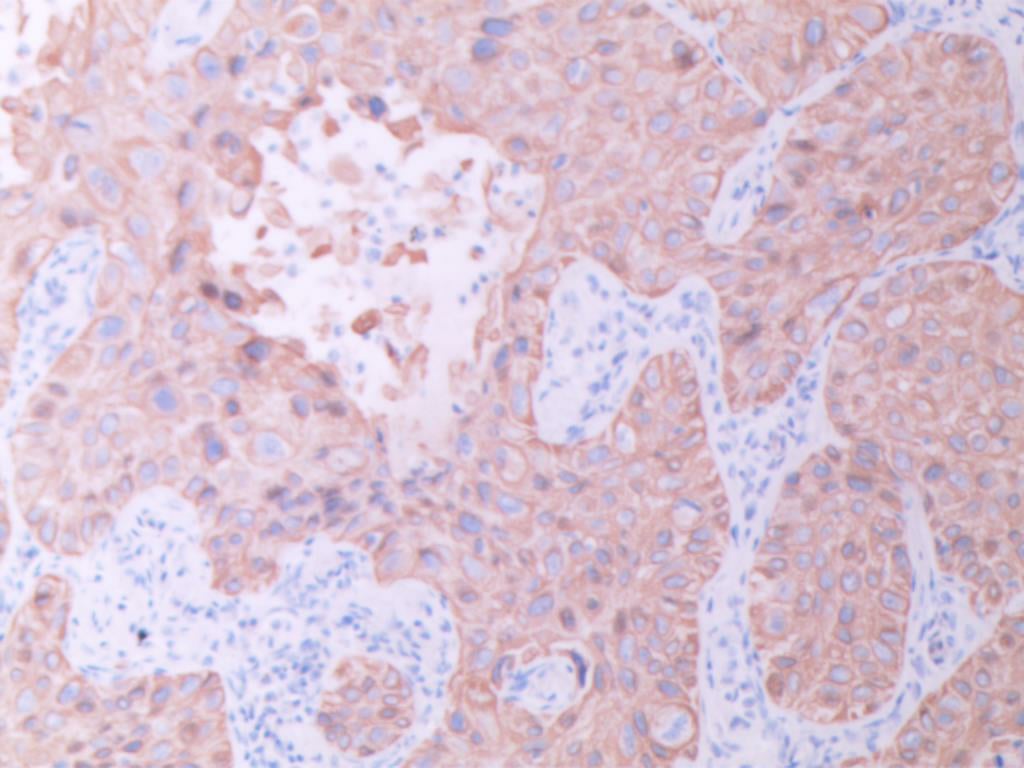

免疫组织化学(IHC)结果显示,肿瘤细胞同时弥漫性阳性表达CK5/6(图E)、p40(图F)、TTF1(图G)和NapsinA(图H)。而CK7、CgA、INSM1、syn、CD56、PAX8和CDX2均不表达。特殊染色黏液卡红灶性染色(图I)。

图E CK5/6弥漫阳性 (SPx100)

图F P40 弥漫性阳性 (SPx100)

图G TTF1 弥漫性阳性 (SPx100)

图H NapsinA弥漫阳性(SPx100)

TTF1和NapsinA通常被认为是肺腺癌的特异性标志物,而p40和CK5/6则是肺鳞癌的特异性标志物。本病例中这四种标志物的弥漫性共表达极为罕见,提示肿瘤具有腺癌和鳞癌的双向分化特征。这种独特的免疫表型使得常规分类变得困难,最终诊断为“具有腺癌和鳞癌双向分化免疫表型特征的非小细胞肺癌”。